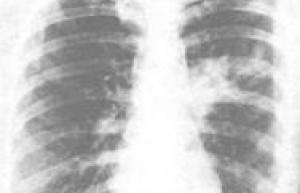

小编导读:间接性肺炎是什么?根本没有间接性肺炎,应该是间质性肺病(InterstitiallungDisease,简称ILD)是以弥漫性肺实质、肺泡炎和间质纤维化为病理基本改变,以活动性呼吸困难、X线胸片示弥漫阴影、限制性通气..

……概念: 支原体肺炎系由肺炎支原体所引起的呼吸道感染,有咽炎,支气管炎和肺炎。发病机理:疾病从上呼吸道开始,有充血,单核细胞浸润,向支气管和肺蔓延,呈间质性肺炎或斑状融合性支气管肺炎。临床表现:一般起病缓渐,有乏力,咽痛,咳嗽,发热,纳差,肌痛。X线显示肺部多种形态的浸润影,..

……最初症状类似于流感,有周身不适,咽喉疼痛和干咳.随疾病进展,症状加重,可出现阵发性咳嗽,且咳嗽时有粘液样或粘液脓性或有血丝的痰液.与典型肺炎球菌性肺炎不同,本病发展缓慢.急性症状一般持续1~2周,随即逐渐恢复.但许多病人可有持续数周的乏力和全身不适症状.本病症状一般较轻且通常可自愈.但少..